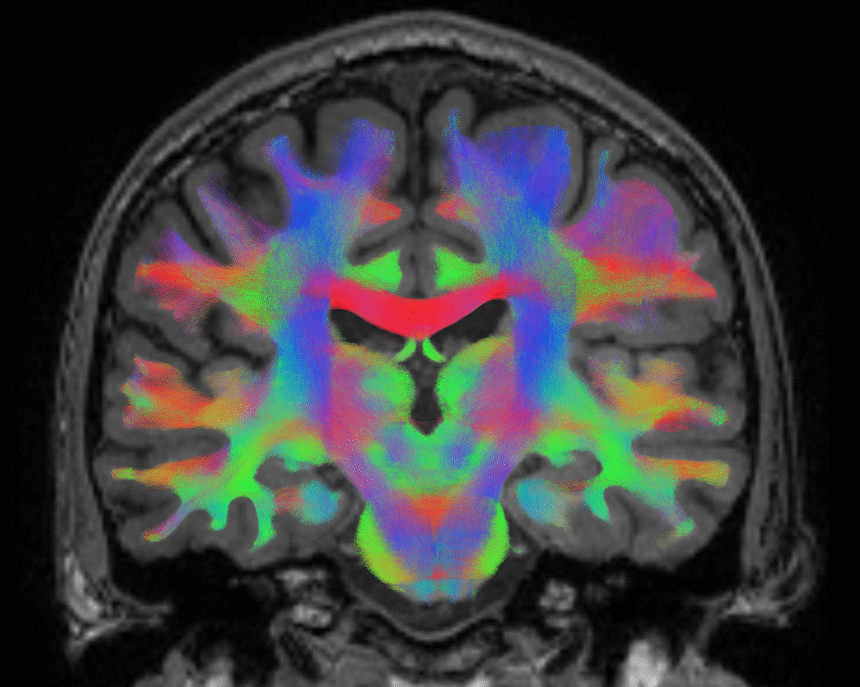

Biosensörler – fark edebilen duyarlı cihazlar devrinin anahtarı.

Biyosensör, belirli bir biyomolekülü seçici olarak tanıyıp bu etkileşimi ölçülebilir bir elektriksel,…